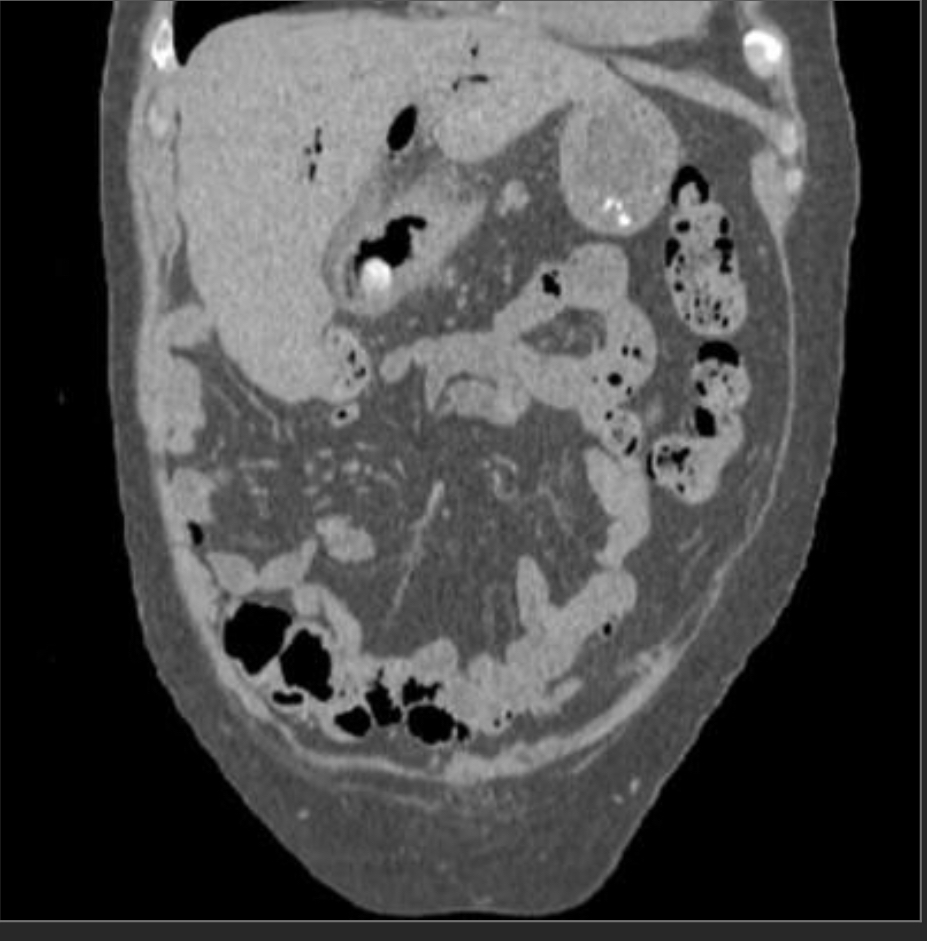

Closed loop obstruction

There is a cluster of fluid-distended loops of small bowel in the pelvis that are notable for relative absence of intraluminal gas, minimal enhancement of their mucosa, infiltrated mesentery, engorged mesenteric vessels and interloop ascites. The distal small bowel is of normal caliber.

—> findings suggestive of ischemia/closed loop include minimal enhancement of the mucosa and engorged mesenteric fat/vessels, and focal ascites.

—> in pt w/appropriate hx could also be a post-op intramesenteric hernia